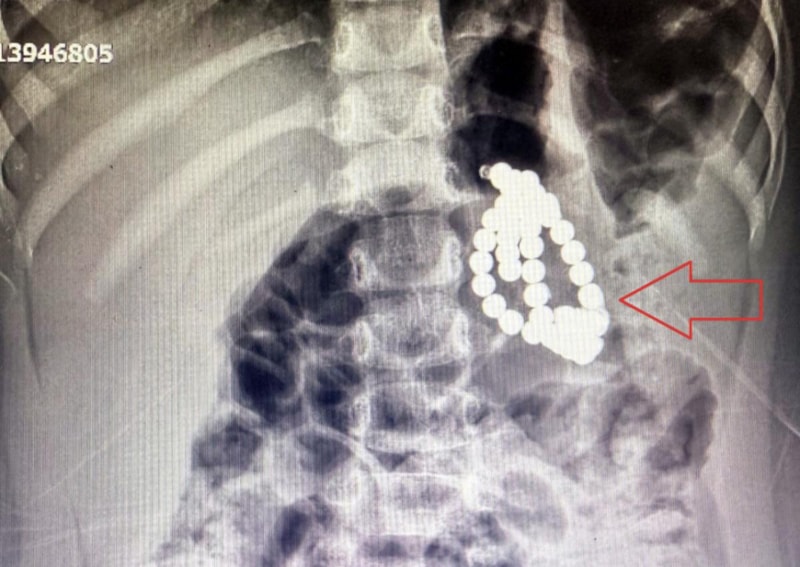

Çekilen röntgende, mide ve bağırsaklarında boncuk benzeri yabancı cisimler tespit edildi.

Aile kızlarının kolye ya da bileklik yuttuğunu düşünürken, doktorlar manyetik boncuklardan şüphelendi.

3 yaşında bir kız çocuğu. Acile mide bulantısı kusma şikayetiyle başvurdu. Röntgende, karında çok sayıda boncuğa benzer yabancı cisme rastlandı. Aile daha çok boncuk, bileklik tarzı plastik birşey yuttuğunu düşünüyordu. Görüntüye baktığımızda, son zamanlarda çok sık rastladığımız magnet boncuk yutma vakalarına benziyordu.